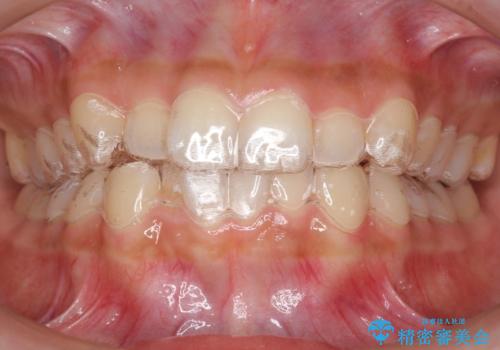

犬歯のねじれ 下の歯のがたがた インビザラインで

- 右上の犬歯のねじれ、下の歯のがたつきを主訴に来院。

インビザラインで歯を抜かずに並べました。

下の前歯のがたがたがそれなりにあったため、リファインメントを行いました。